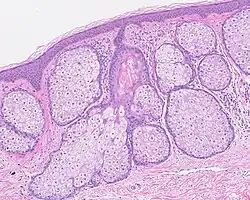

Les glandes sébacées ont une architecture acinaire (en forme de grappe de raisin) et n'ont pas de lumière propre. Elles sont composées de sébocytes matures, dont la sécrétion est le résultat de leur mort par apoptose[pas clair], ce qui revient à une sécrétion holocrine. Le remplacement des cellules est assuré par les cellules de la matrice reposant sur la membrane basale[5].L'annexe pilo-sébacée constituée du follicule pileux, des glandes sébacées et des muscles arrecteurs du poil résulte d'une invagination épithéliale[4].

Multiples glandes sébacées volumineuses réalisant une hyperplasie sébacée.

Multiples glandes sébacées s'abouchant à un follicule pileux.